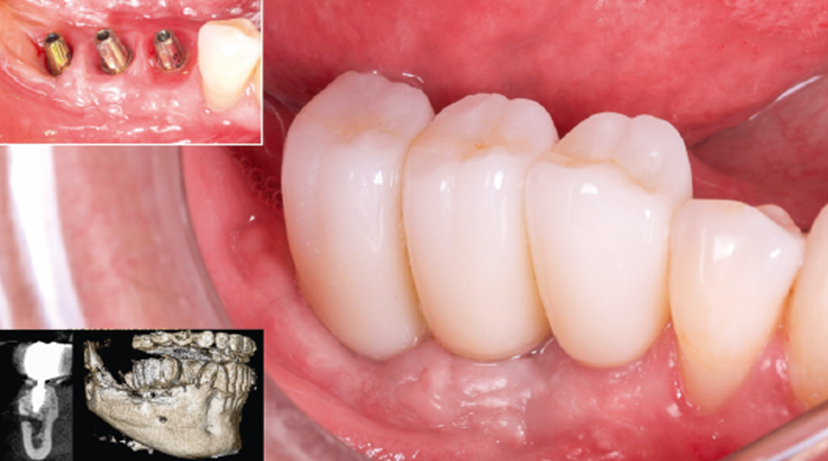

Após três meses, constatou-se a neoformação óssea adequada.Assim, foram instalados três implantes cone-morse Maestro (Implacil Osstem) com estabilidade primária satisfatória e aproximadamente 20 Ncm de torque de inserção (Figura 8). Após a instalação dos implantes, para ganho de volume tecidual e diminuição da remodelação do tecido ósseo, foi realizada a colocação de enxerto ósseo xenógeno com colágeno (Extra Graft, Implacil Osstem / Figura 9). Três meses após a osseointegração, os implantes foram reabertos para instalação dos pilares protéticos (Ideale, Implacil Osstem) e confecção das coroas provisórias, seguidas da finalização com as cerâmicas definitivas unitárias em zircônia monolítica após mais três meses de terapia (Figuras 9 e 10).

Figura 8 – Reabertura após o período de três meses para a instalação de três implantes Maestro (Implacil Osstem) de 3,5 × 10 mm.

Figura 9 – Cobertura da área enxertada com substituto ósseo xenógeno (Extra Graft, Implacil Osstem).

Figura 10 – Instalação de pilares Ideale (Implacil Osstem) e provisorização após três meses da instalação dos implantes e finalização das cerâmicas após seis meses. Controle de dois anos em TCFC.